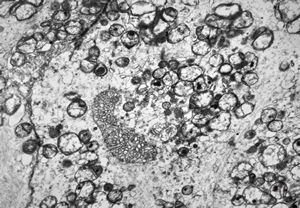

F,50y. | progressive multifocal leukoencephalopathy- viral particles in a glial cell

F,50y. | progressive multifocal leukoencephalopathy- viral particles in a glial cell

F,50y. | progressive multifocal leukoencephalopathy- viral particles in a glial cell